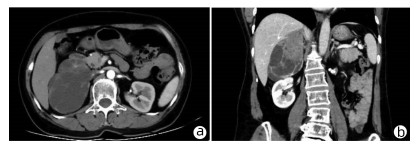

Solitary fibrous tumor of the liver: A case report

2022, 38(3): 632-633. DOI: 10.3969/j.issn.1001-5256.2022.03.026

Abstract(803) HTML (221) PDF (2657KB)(58)

Abstract: